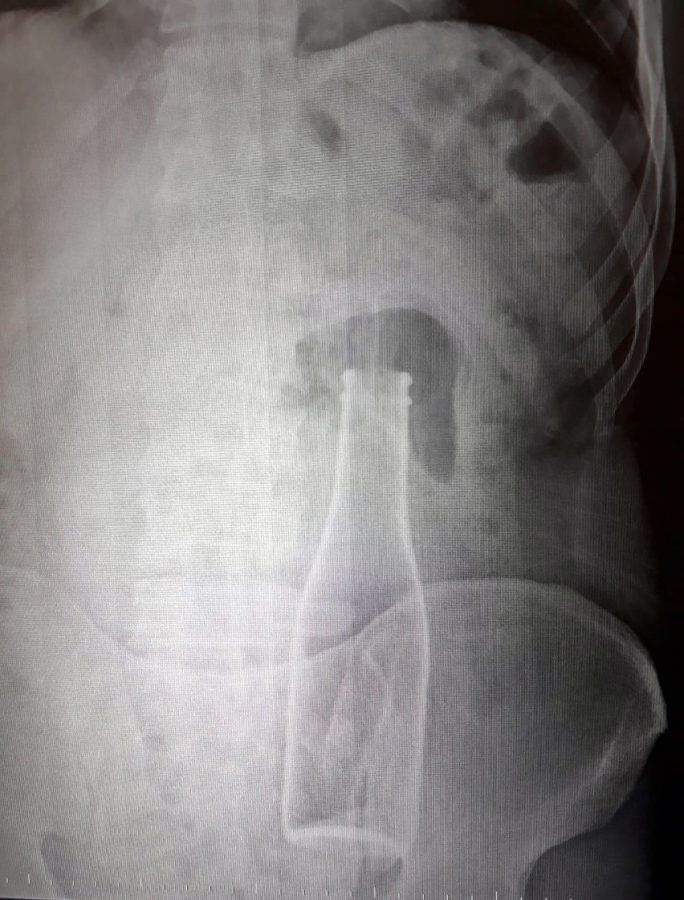

Dün akşam saatlerinde Karaman Eğitim ve Araştırma Hastanesi'ne gelen A.E., doktorlara karın ağrısı şikayetinin olduğunu söyledi. Çekilen röntgen filminde A.E.'nin kalın bağırsağının bulunduğu bölgede şişe olduğu tespit edildi. A.E.'nin makatından sokulduğu belirlenen soda şişesi, yaklaşık 1 saat süren ameliyatla çıkarıldı.